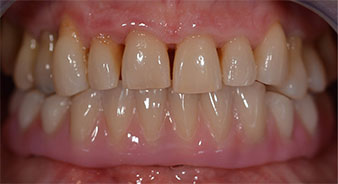

Die 64-jährige Patientin wurde mit einer Unterkiefer-Restbezahnung 38, 33 und 43 und einer klammerbefestigten Interimsprothese im Unterkiefer vorstellig (Abb. 1 und 2).